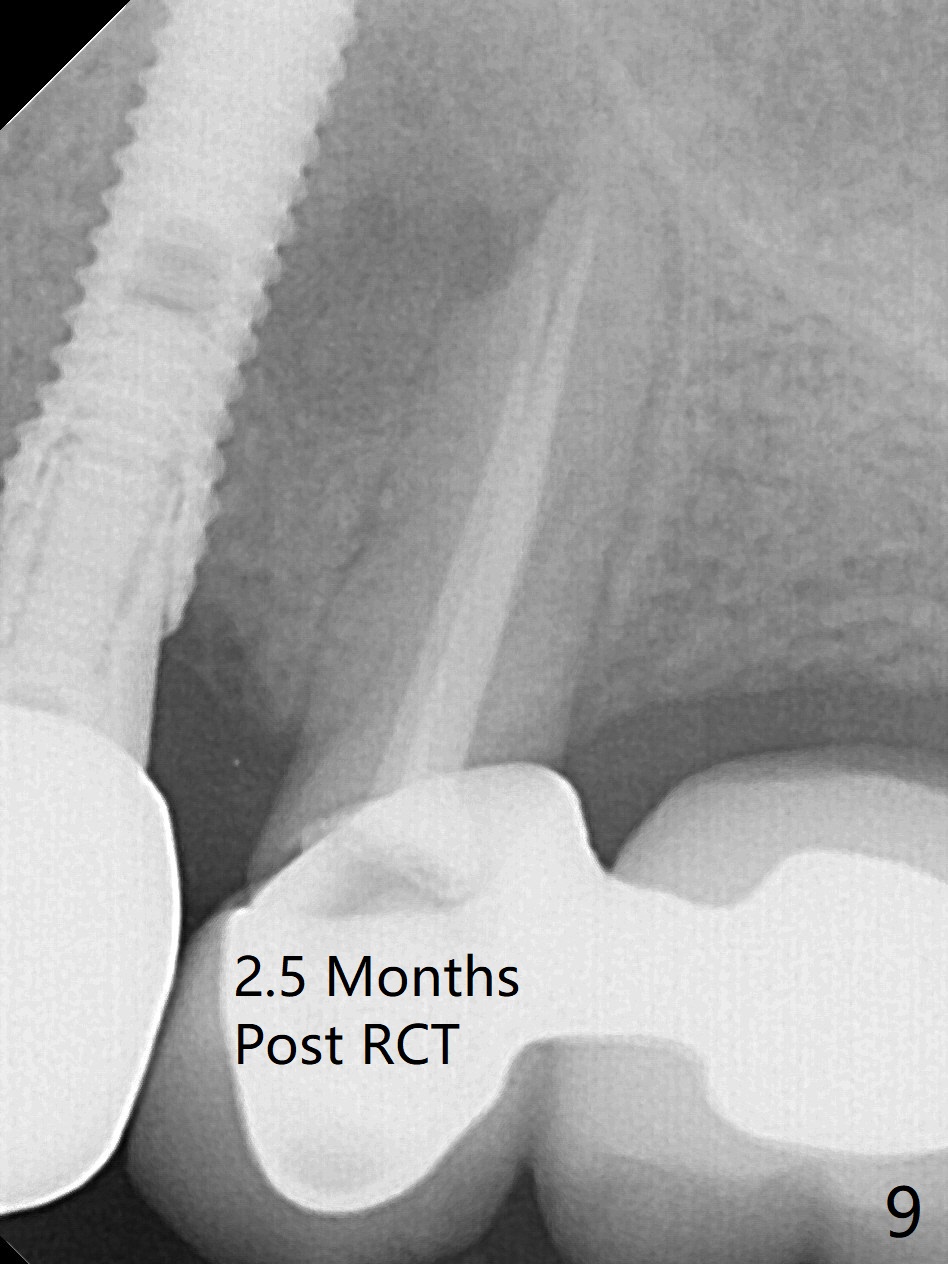

After extraction of the oval-shaped residual roots at #12 (Fig.1), osteotomy is initiated in the palatal socket for 18 mm; since the root of the canine curves distal (Fig.2 red dashed line), the osteotomy cannot afford to move mesial and extend more apical. A 3.8x15 mm implant is placed with > 50 Ncm (Fig.3). With immediate placement of a 4.5x4(3) mm abutment, an immediate provisional is fabricated to close the sockets (Fig.4 P). The provisional has clearance from the RPD clasps (Fig.5). In fact the implant could be longer, as shown by immediately postop panoramic X-ray (Fig.6). The implant seems to be osteointegrated 3 months postop (Fig.7). The tooth #13 is symptomatic with caries (Fig.8 C) 7 months post #12 crown cementation; the #13-15 FPD dislodges. The upper left quadrant is cold and hot sensitive 2.5 months post RCT (Fig.9); although there is mild percussion at #13, pulpal test shows that the tooth #15 has lingering pain. The FPD was recemented temporarily after RCT; it cannot be removed. The implant crown has been loose for several months during the pandemic before he returns 2 years 7 months post cementation. In fact the abutment has been not seated completely (from Fig.3 to 9). The crown/abutment is removed from the mouth; the crown is sectioned and separated from the abutment; the latter is reseated, but incompletely (Fig.10 <). With suspicion of the mesial crestal contact, profile drills 4.6 and 5.5 mm are used without effect. A new (old probably being worn) and longer (easy to turn in the narrow space) abutment is finally seated completely (Fig.11 (no gap)). After occlusal adjustment, abutment level impression is taken for a new crown.